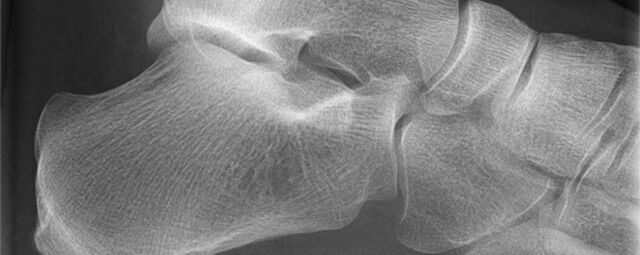

Konventionelles Röntgen

Der Begriff Röntgen, oder auch Röntgendiagnostik bezeichnet ein Verfahren in der Radiologie, bei dem von einer Röntgenröhre elektromagnetische Wellen (Röntgenstrahlen) durch die zu untersuchende Körperregion des Patienten gesendet werden. Je nach Dichte der Gewebeart des Körpers (z.B. Knochen oder Lunge) werden die Röntgenstrahlen im Körper unterschiedlich stark abgeschwächt. Ein digitaler Detektor empfängt dann die Röntgenstrahlen, die in abgeschwächter Form den Körper wieder verlassen haben. Daraus wird das Röntgenbild erzeugt.

Die Röntgenuntersuchung ist weiterhin eine unverzichtbare Basisdiagnostik. Viele Fragen können in der medizinischen Diagnostik mit einer konventionellen Röntgenaufnahme geklärt werden.